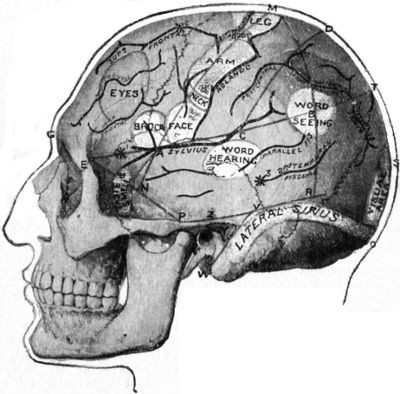

325 179.Relations of the Motor and Sensory Areas to the Convolutions and to Chiene's Lines

330 180.Diagram of the Course of Motor and Sensory Nerve Fibres

333 181.Chiene's Method of Cerebral Localisation